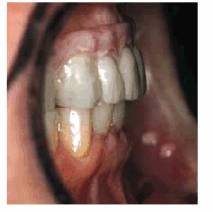

procedure can be seen in Figures 17-8A

and B 17-8C 17-8D 17-8E 17-8F 17-8G 17-8H and I, which show a 45-year-old man with

evidence of gingival and incisal abrasion, erosion, and abfraction. It is

Figure 17-8A and B: This 45-year-old man shows extreme tooth loss due to combination lesions both gingivally and incisally of abrasion, erosion, and abfraction.

Figure 17-8H and I: Although early intervention is the best approach, restoring the defects at any point is both functionally and esthetically beneficial. Bonding is especially effective in preventing further damage to the tooth surface it covers.